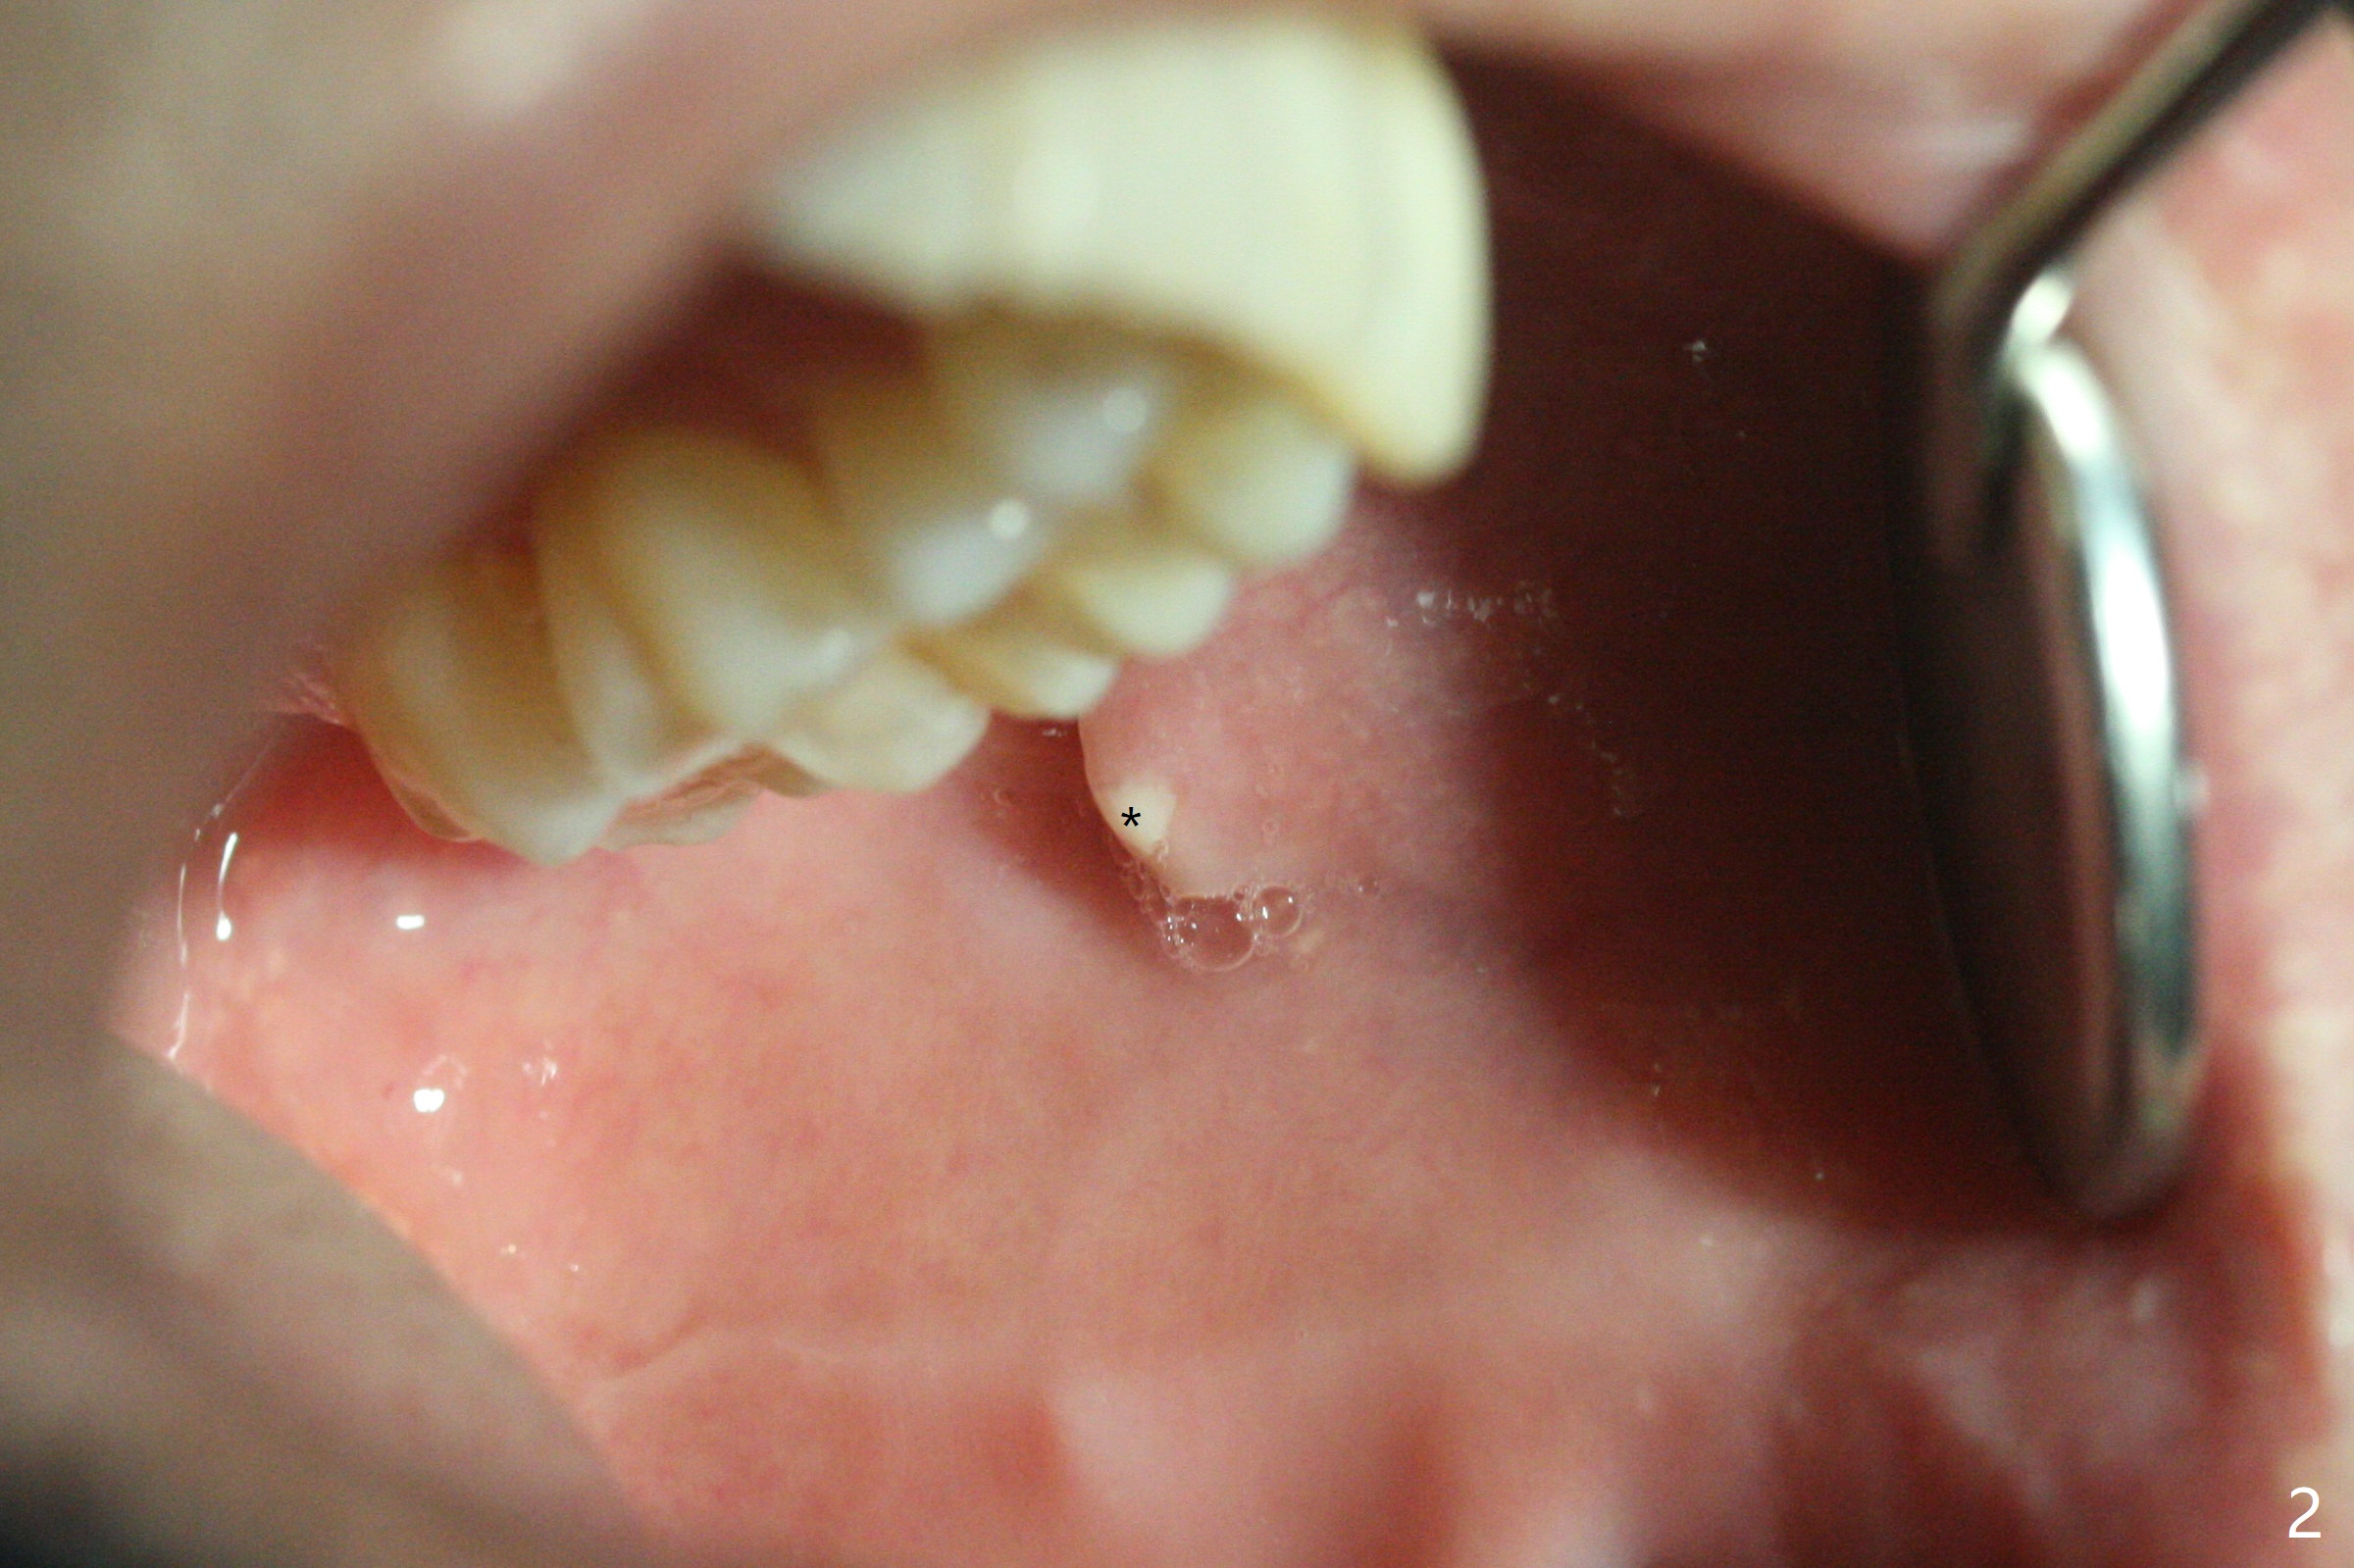

50岁男左侧面部肿痛两个月(图一),服用头孢霉素,最后家庭医生怀疑腮腺炎,需要口外医生诊治,他昨天来我们诊所,口内检查表明左侧腮腺导管口红肿,少量脓液(图二:*),导管口远中粘膜下好像有硬块,便拍摄X光片,显示~4毫米结石(图三),病人积极要求马上治疗,但是当时没空,他只好今天回来。来时说痛极了,口外肿胀中心(图一:箭头)反而硬。口内浸润麻醉后,在导管口远中做一个小切口(图四:黑线),沿着导管方向,锐性钝性分离不久,发现结石,取出(图五)。挤压口外肿胀中心,大量脓液从口内切口流出(图六)。手术当天晚上病人汇报疼痛消失。术后八天在腮腺深部才有压痛,口内导管口周围正常(图七)。Return to Professionals 植牙,导板与正畸 Xin Wei, DDS, PhD, MS 1st edition 12/23/2020, last revision 01/05/2021